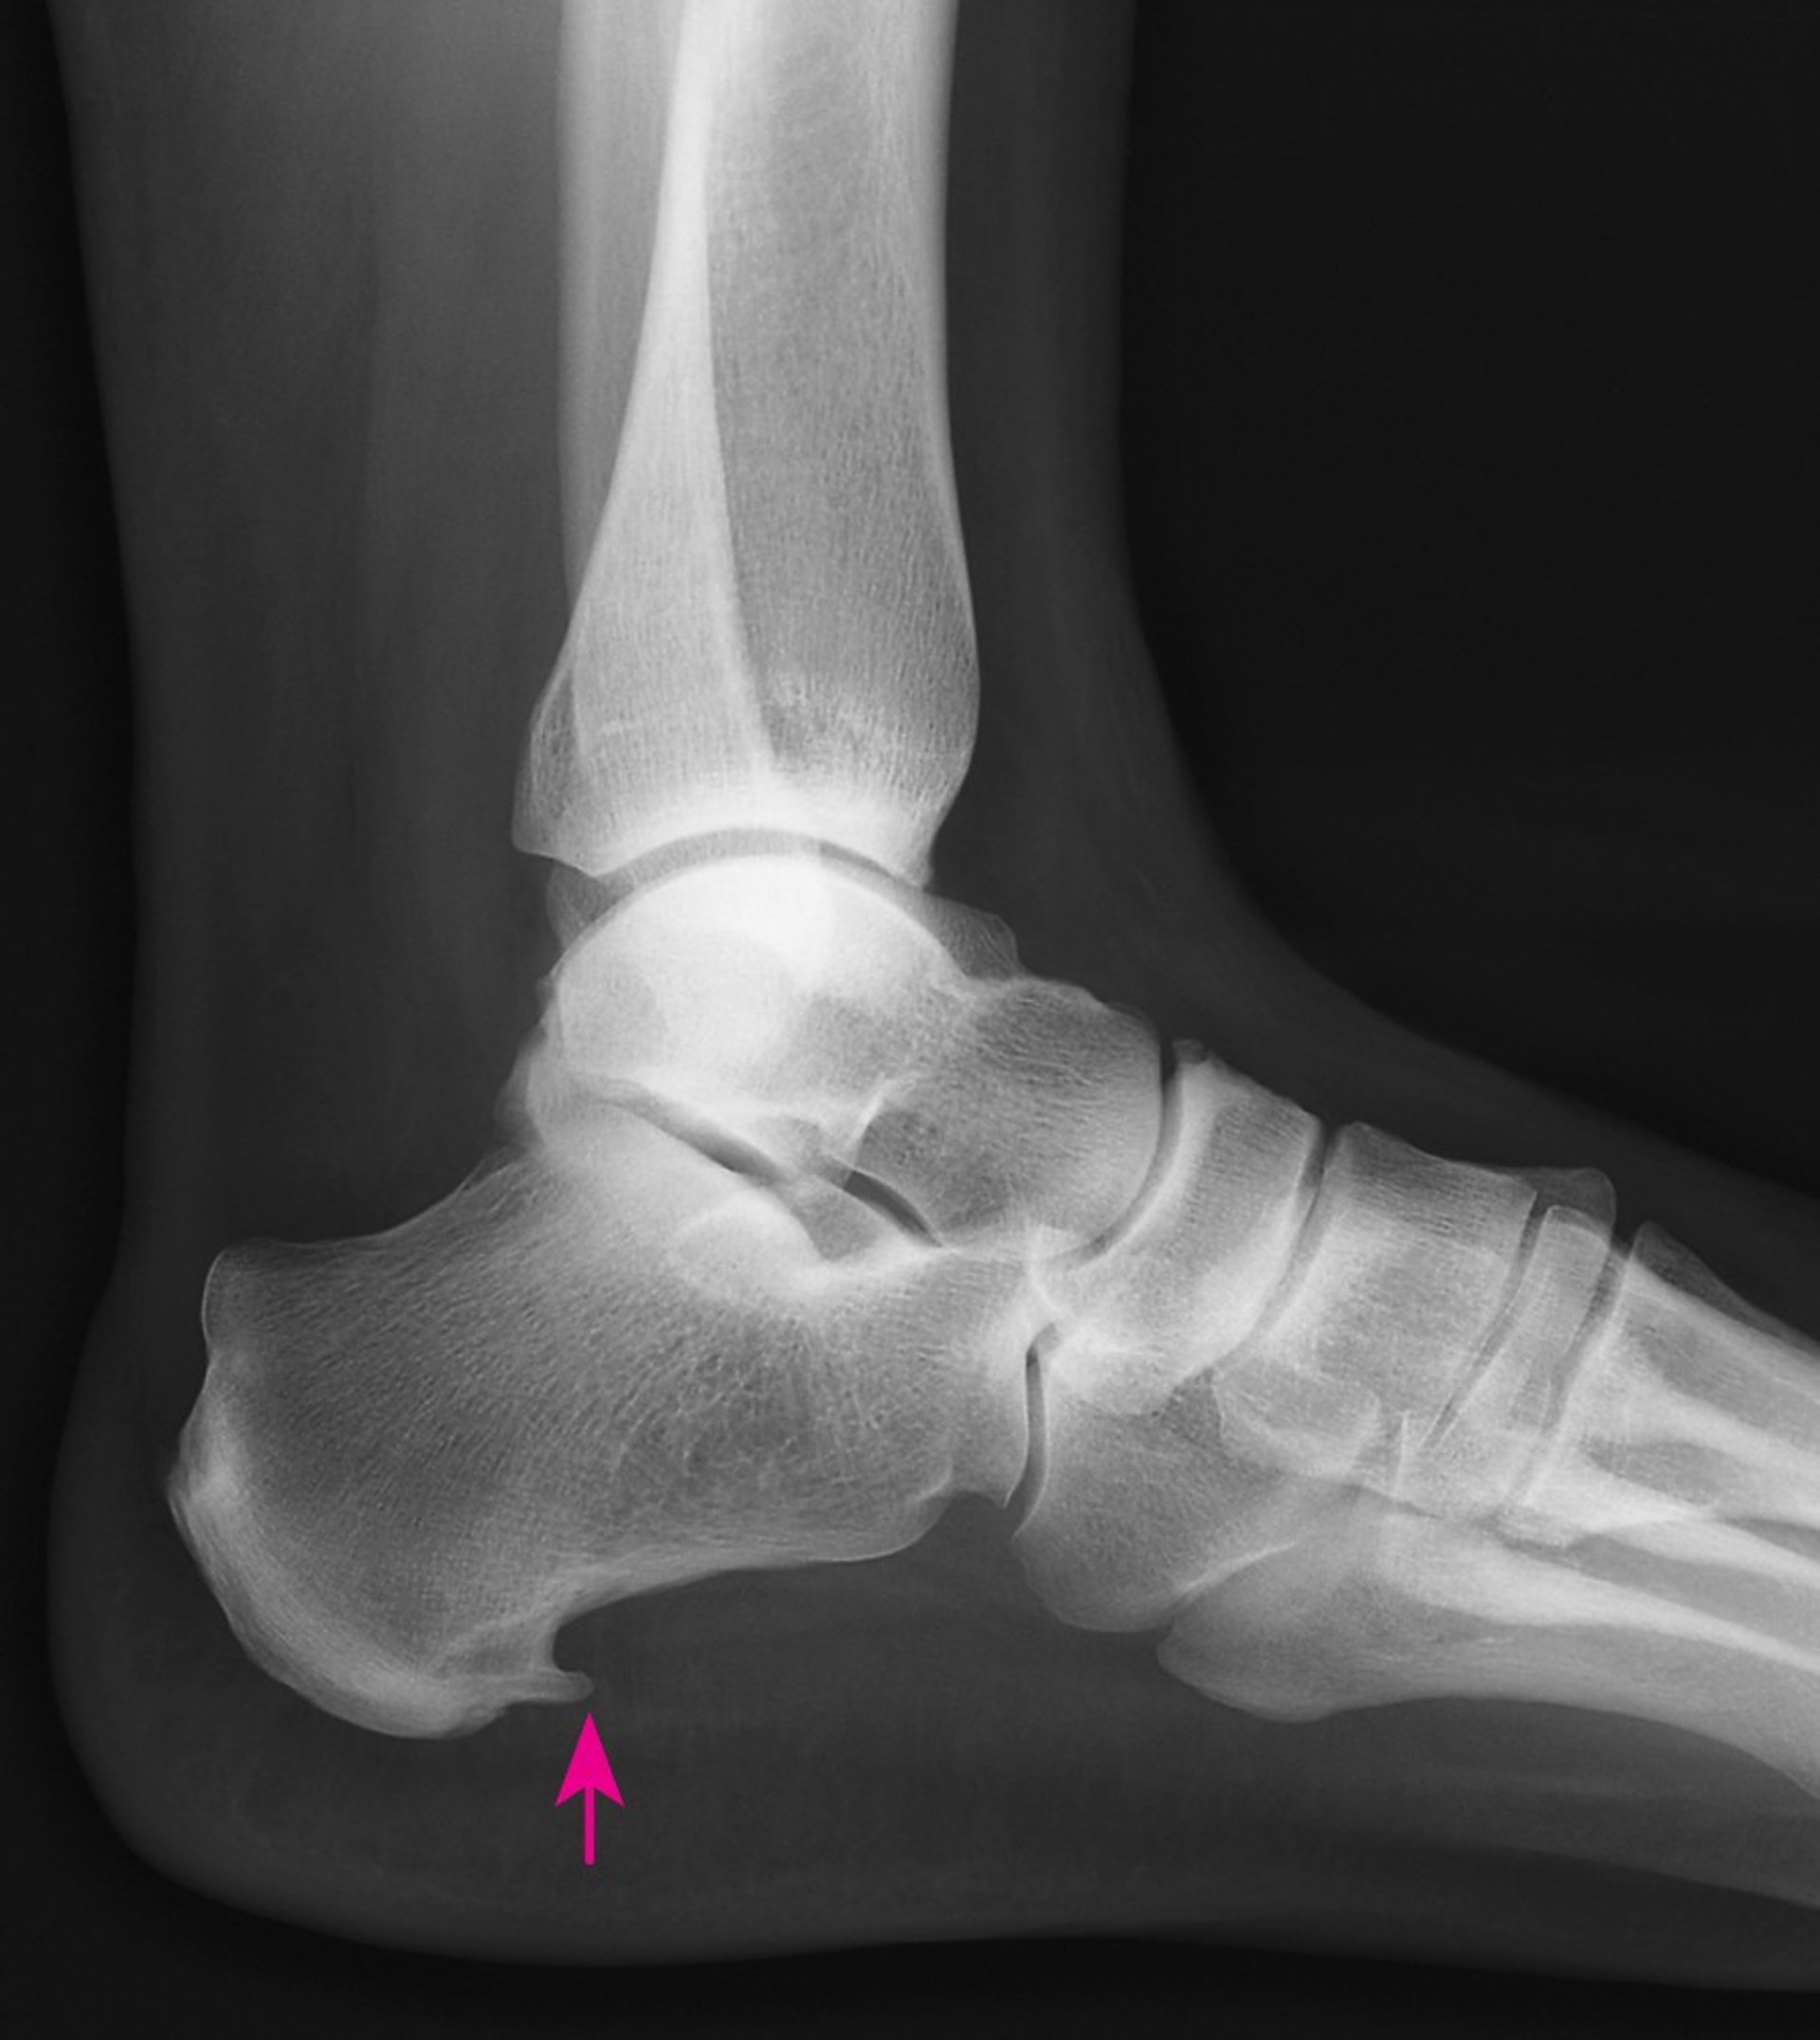

This x-ray shows a heel spur, the pointed growth of extra bone on the bottom of the heel bone (arrow).